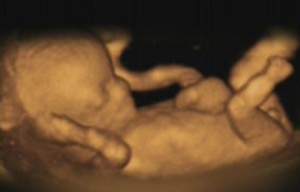

El departamento de Sanidad británico investigará los hechos denunciados por el Daily Telegraph que filmó en secreto a médicos que accedieron a llevar a cabo abortos porque la madre no quería el sexo del bebé.

Según este diario, los doctores accedieron a dar luz verde a interrupciones de embarazo porque la madre no quería el sexo del bebé. El ministro de Sanidad ha recordado que el aborto selectivo por sexo es ilegal y un error moral.

La sociedad protectora de bebés no nacidos ha denunciado que este hecho es consecuencia inevitable del fácil acceso al aborto.